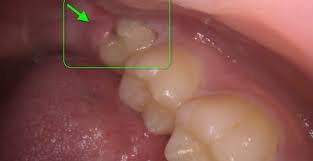

The third molars, commonly called wisdom teeth, are the final teeth to erupt, typically between the ages of 17 and 25. While some people are lucky enough to have them emerge without any issues, for many, these teeth can become a significant source of discomfort and a threat to overall health. The most common reason for a wisdom tooth removal brampton is that they become impacted. An impacted wisdom tooth is one that doesn’t have enough room to grow in properly and is stuck in the jawbone or under the gum tissue.

- Damage to Neighboring Teeth: As an impacted wisdom tooth attempts to grow, its roots can press against the molar next to it, potentially causing damage to its structure and leading to

boneloss. - Cyst Formation: In rare cases, a

cystcan form around the impacted wisdom tooth. This fluid-filled sac can cause damage to the surrounding jawbone, teeth, and nerves. - Difficulty Chewing: In some cases, the improper growth of a wisdom tooth can interfere with normal chewing and bite alignment.